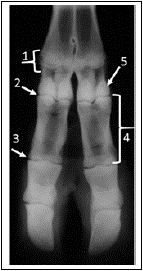

Analise a imagem a seguir.

As estruturas enumeradas sequencialmente de 1 a 5, no exame radiográfico do dígito de um bovino em exposição dorsopalmar, são: